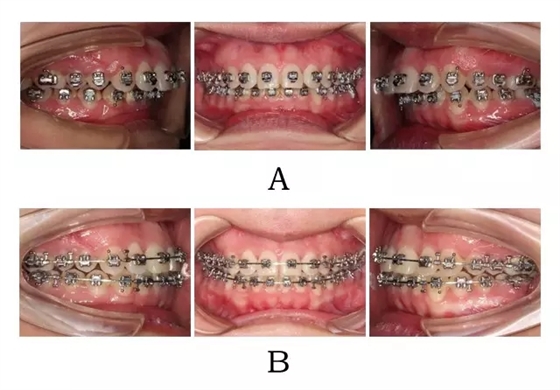

?首選 SGTB,年齡可適當(dāng)放寬至生長發(fā)育停止后的年輕成人。矯形機(jī)制是后移前突的上頜并釋放后退的下頜(圖4-2;4-3)。

圖4-2:混合I型突面畸形SGTB矯形及后期常規(guī)固定矯治。

(A)SGTB矯形 (B)后期固定矯治

Figure 4-2. SGTB therapy for merged prognathism (Type I). (A) SGTB orthopedics at early stage.(B) Fixed orthodontics at late stage.